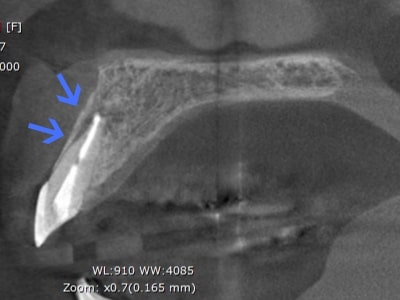

症例3歯性副鼻腔炎

Before

左上3番の疼痛・腫れを主訴として来院

CT撮影により、歯性副鼻腔炎と診断

After

約7ヶ月間の根管洗浄・殺菌により、病巣も消失し、副鼻腔の肥厚もなくなり、歯槽骨の再生が得られた